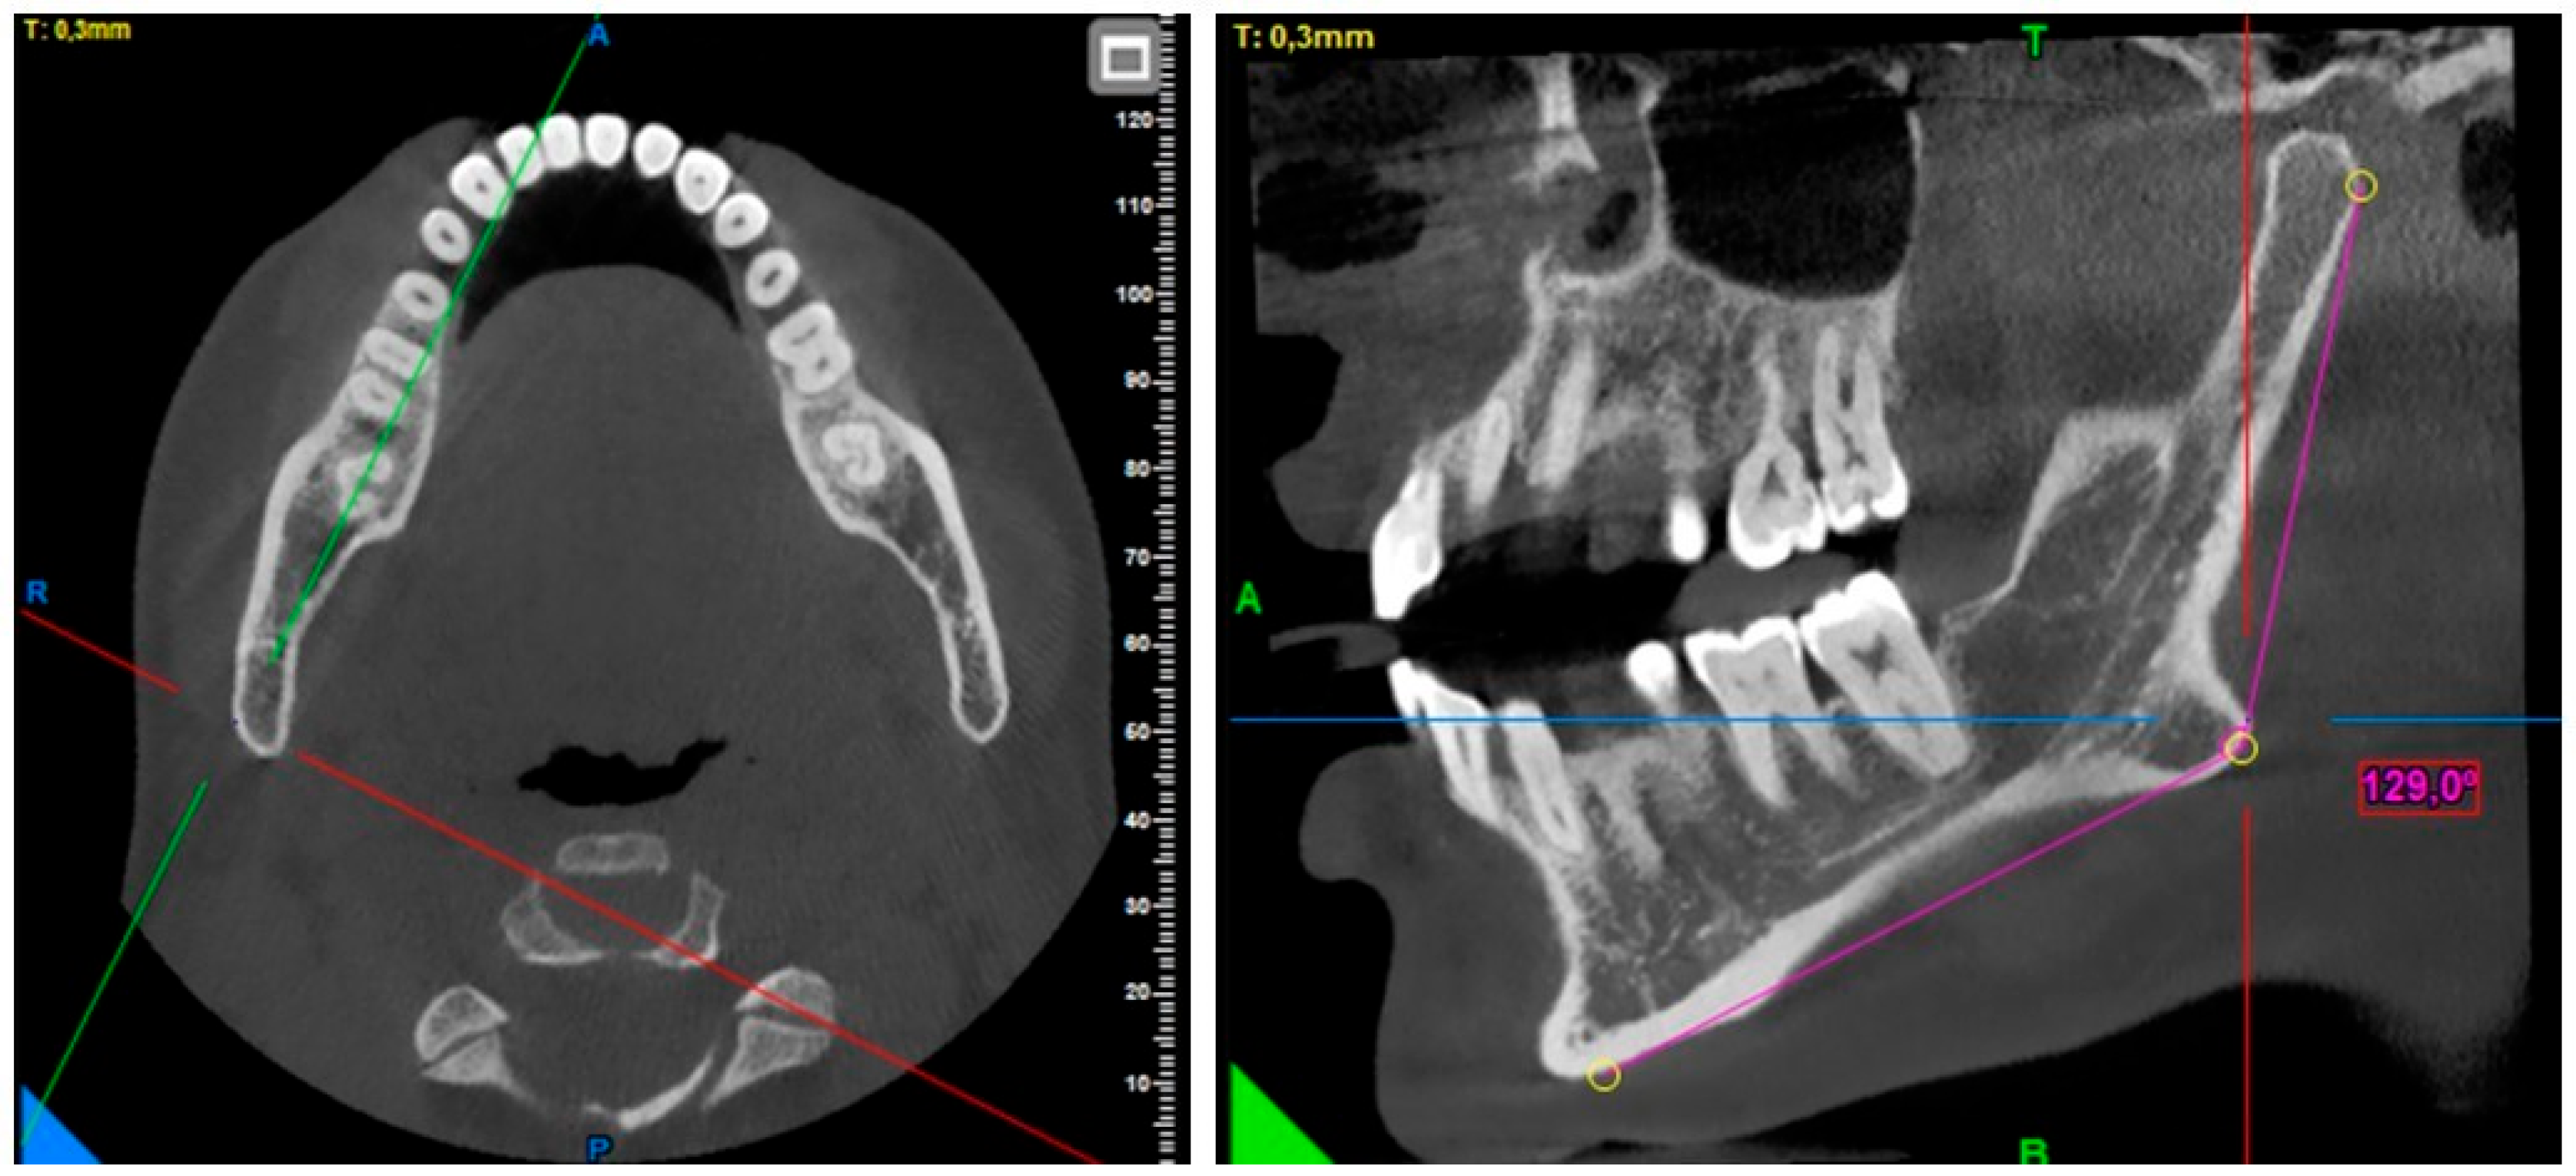

A Morphometric Evaluation of the Mandibular Condyle, Coronoid Process, and Gonial Angle: Age and Gender Differences in CBCT Imaging

2. Materials and Methods